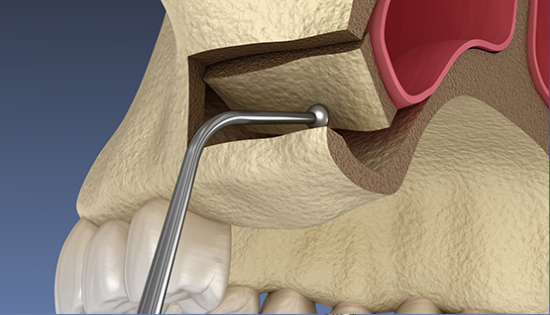

임플란트 수술시, 상악동과 잇몸뼈 사이에 뼈가 남아 있지 않았을 때 상악동막을 들어올리고 빈 공간에 뼈를 이식하여 임플란트 식립을 위한 공간을 확보하는 수술을 상악동 거상술이라 합니다.

밀도가 높고 두꺼운 턱뼈가 구성된 아래턱과는 달리 위턱은 얇은 뼈 위에 코와 광대 사이 빈 공간에 식립해야 하는 고난도 수술로 임플란트 수술 경험이 많은 의료진에게 받는 것이 중요합니다.

상악동거상술 시술과정

상악동거상술은 고난도 수술로 임플란트 수술 경험이 많은 의료진에게 받는 것이 중요합니다.

뼈이식 / 임플란트 식립공간 확보

잇몸을 절개하고 난 후 뼈를 넣고 상악동을 들어 올릴만한 작은 통로를 만들어 뼈이식할 공간과 임플란트 식립할 공간을 확보합니다.